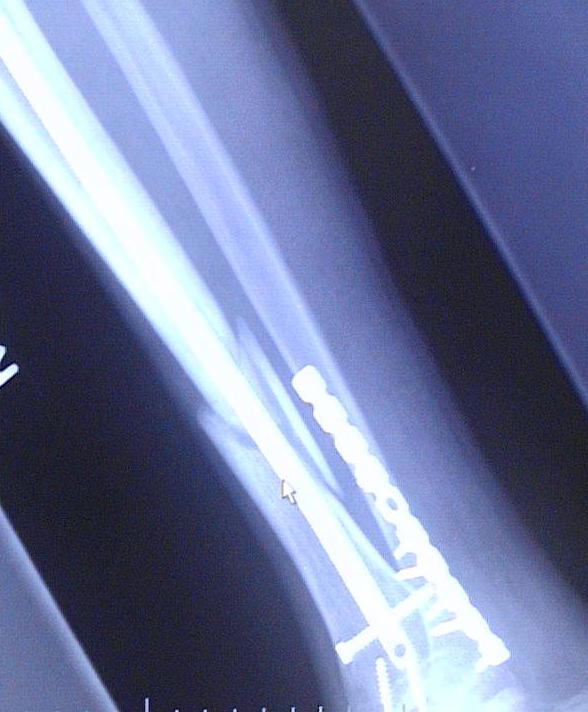

This is Diesel's X-ray's from 9-30-04. He broke hiz tibula on June 21, 2004 doing a 12 o'clock wheelie. Clutch slipped and he flipped over the handle bars and landed ALL hiz weight on hiz right leg causing it to snap.

He just got hiz 3rd cast removed and found out that the bone is not progressing. He now has an walking cast on with a bone stimulator (to maximize circulation to that area) which he will most likely have for the next 6 months. As you can see in the X-Ray's he has a metal plate on the anterior side of hiz ankle where he broke it in 2 places. You can see where the tibula broke and how it is not healing. He has 13 screws and a titanium rod throughout the tibula. Price you pay for being a Stunter!

He just got hiz 3rd cast removed and found out that the bone is not progressing. He now has an walking cast on with a bone stimulator (to maximize circulation to that area) which he will most likely have for the next 6 months. As you can see in the X-Ray's he has a metal plate on the anterior side of hiz ankle where he broke it in 2 places. You can see where the tibula broke and how it is not healing. He has 13 screws and a titanium rod throughout the tibula. Price you pay for being a Stunter! "INSANE STUNTERZ"